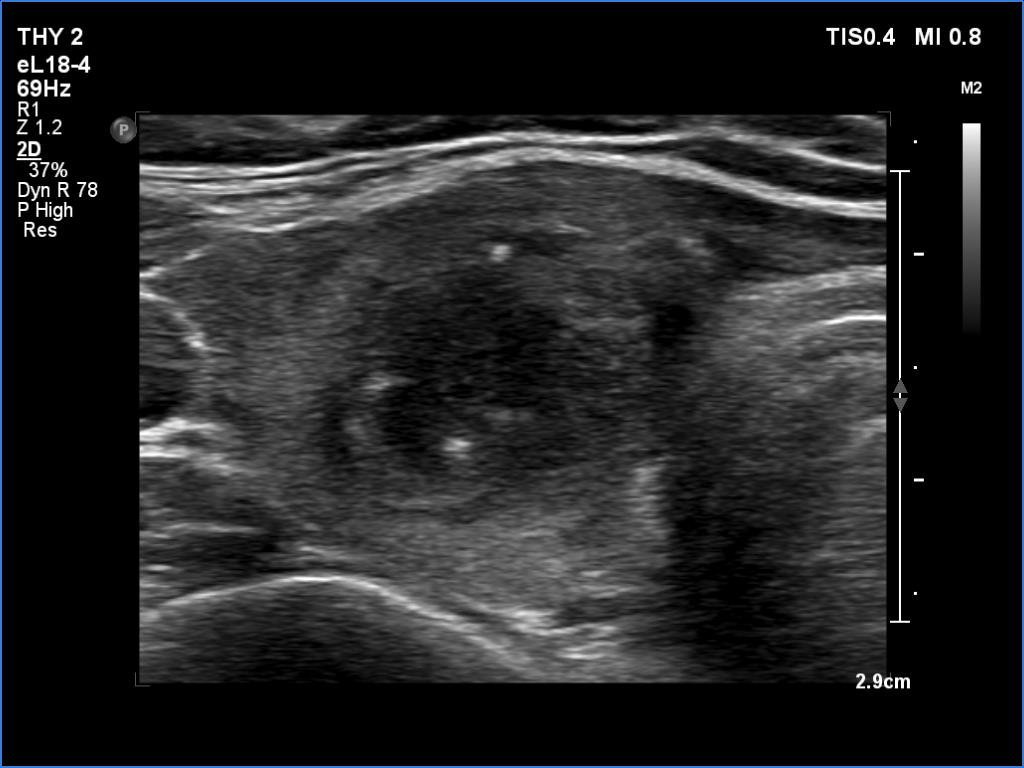

Ultrasonography revealed an echonormal thyroid. There was dominantly moderately hypoechoic nodule in the right lobe. Some parts of the lesion were deeply hypoechoic, and a few small cystic chambers were also within. The nodule presented with irregular shape and borders and had intranodular echogenic figures, primarily granules.

It is ambiguous how to interpret the echogenic figures. Although the presence of irregular shape and borders increases the likelihood that the echogenic granules are indeed microcalcifications, comet-tail artifacts must be also considered.

It is worth comparing the images recorded by using different settings. By using harmonization, we lose the details of very hypoechoic areas. Essentially, the latter seem to be anechoic.